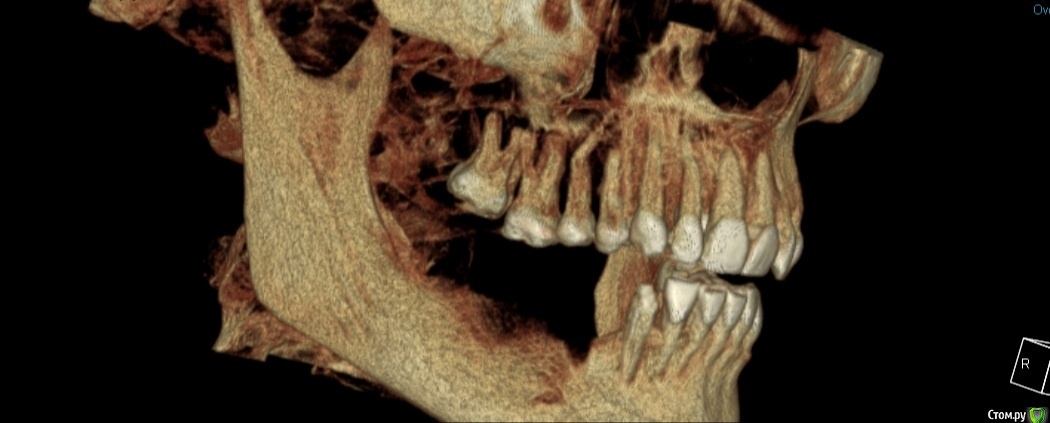

Екатерина Ч. Опубликовано 10 октября, 2020 Поделиться Опубликовано 10 октября, 2020 Здравствуйте. Хочу сделать имплантацию зубов. Нужно ли будет наращивать костную ткань Ссылка на комментарий

Nazim_NV86 Опубликовано 10 октября, 2020 Поделиться Опубликовано 10 октября, 2020 (изменено) Здравствуйте. Срезы(сечения) нужны и желательно с измерениями. Даже просто вертикально и горизонтально по 5мм нарисовать чтоб масштабы были понятны. Изменено 10 октября, 2020 пользователем Nazim_NV86 1 Ссылка на комментарий